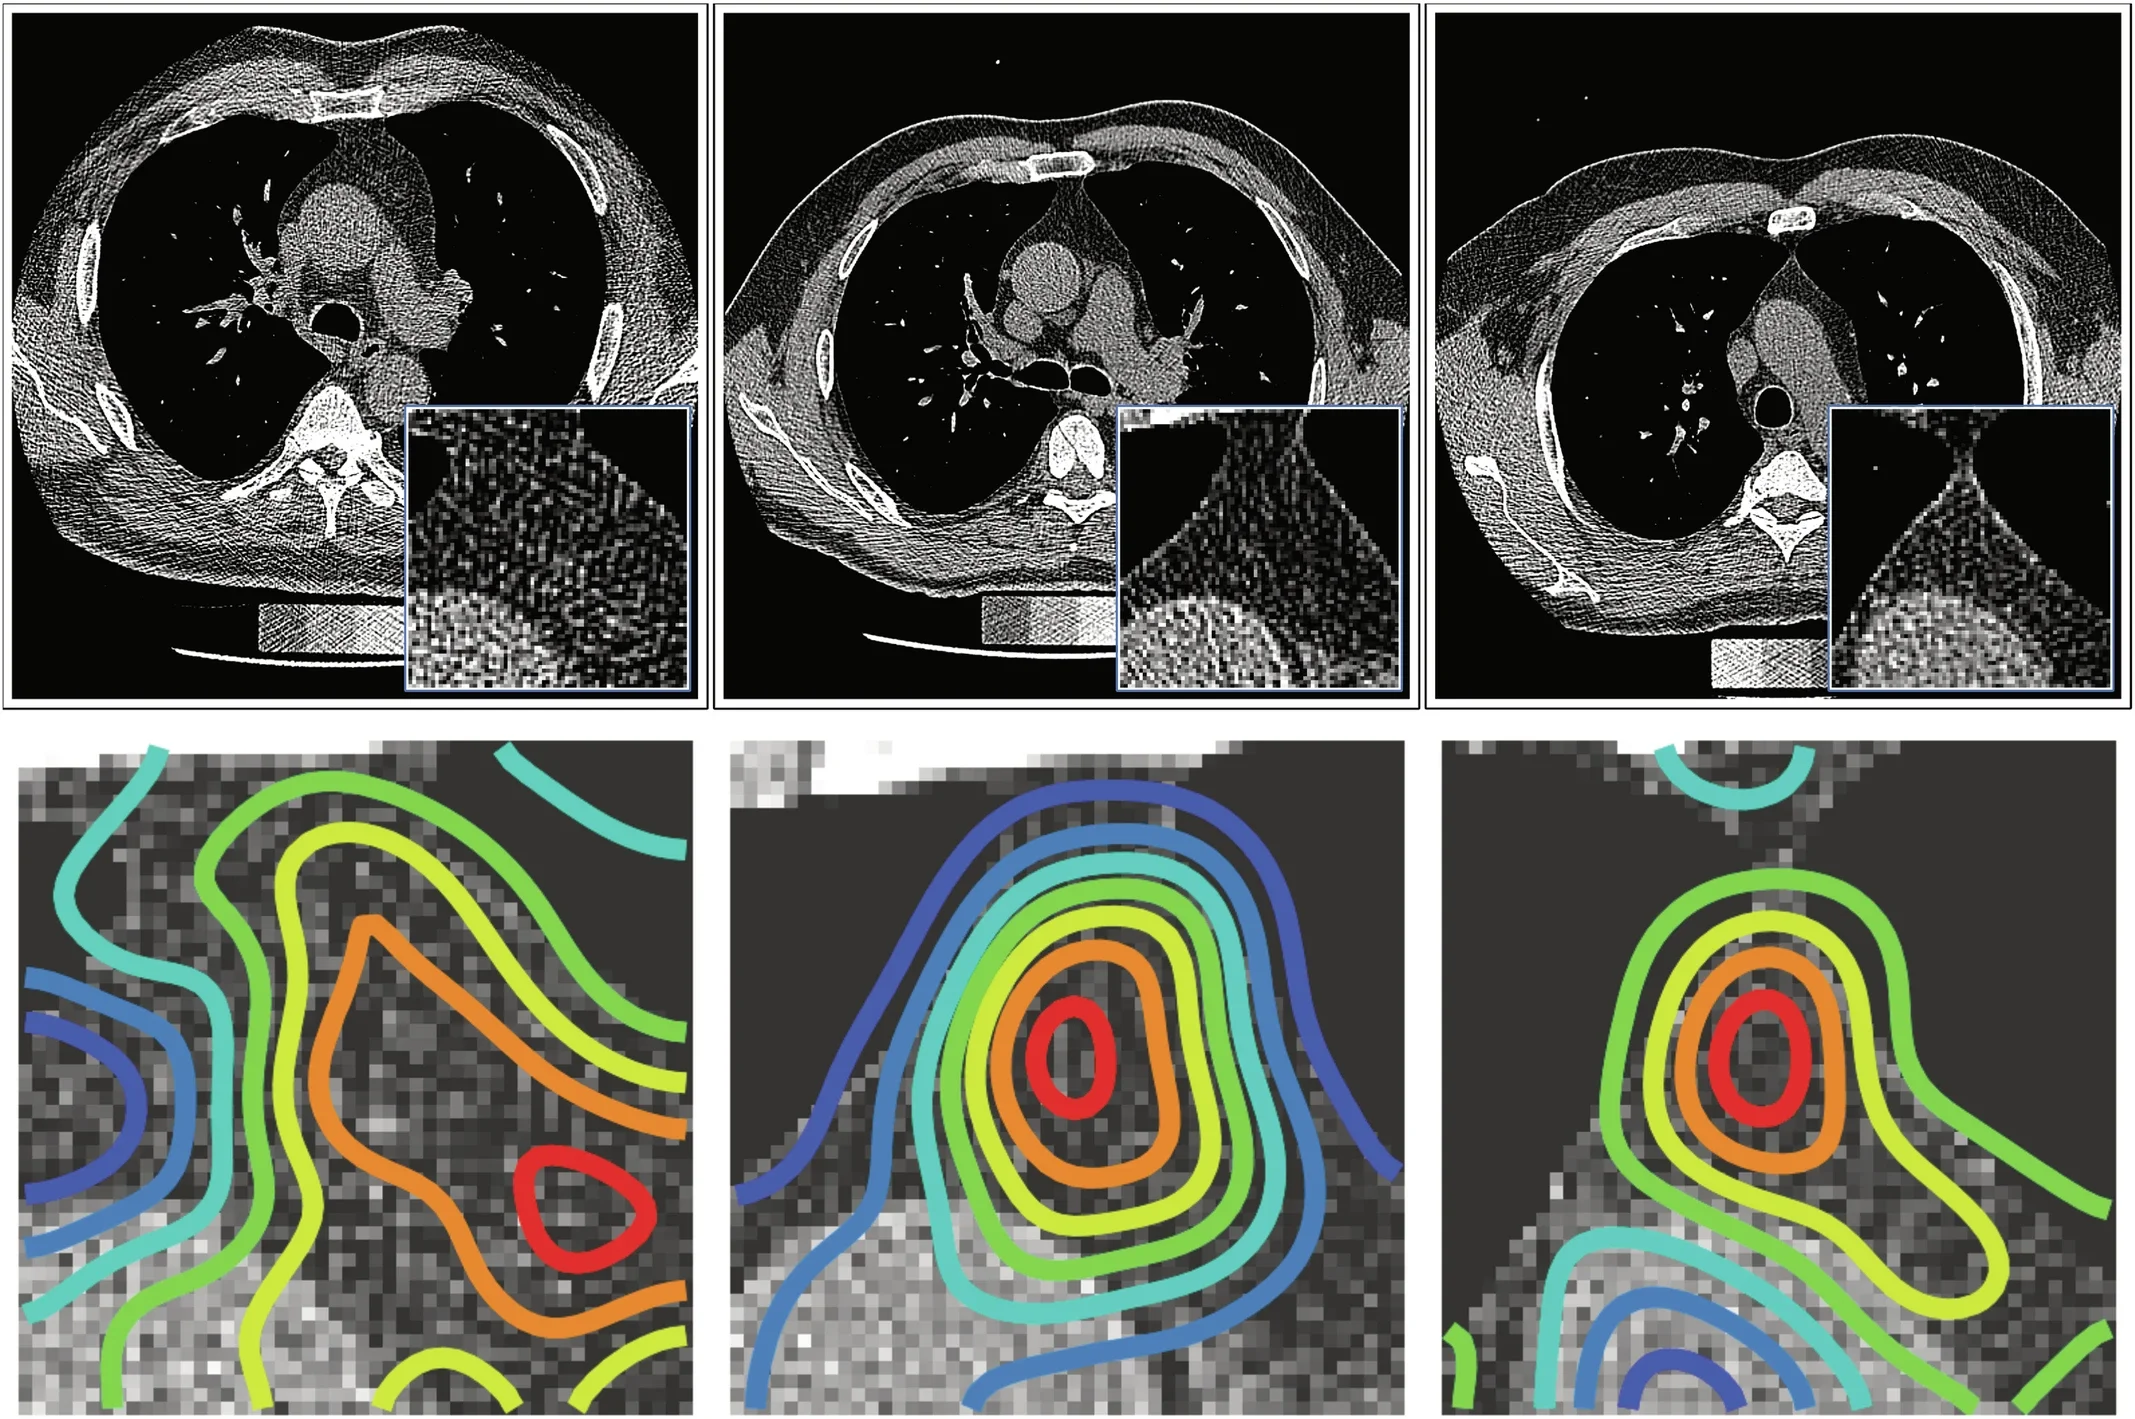

In the first study, the researchers analyzed CT scans from 27,612 adults drawn from two large groups: 25,031 people in the National Lung Screening Trial and 2,581 in the Framingham Heart Study. They used a deep learning system, developed on a separate dataset of 5,674 scans, to estimate “thymic health” based on the organ’s radiographic appearance.

The authors are careful here. They describe thymic health as an imaging-based proxy for thymic functionality, not a direct measure of it.

In an independent cohort from the TRACERx lung cancer study, involving 464 treatment-naive patients, higher thymic health was linked to higher levels of signal joint T cell receptor excision circles, or sjTRECs, a marker of thymic output. Patients with higher thymic health also had greater T cell receptor diversity in blood and signs of stronger tumor-specific immune activity.

That helps connect the scans to something more than appearance. The thymus is where T cells mature. If healthier thymic tissue means more sustained T cell production or diversity in adulthood, it becomes easier to see why the organ might matter in aging and cancer.